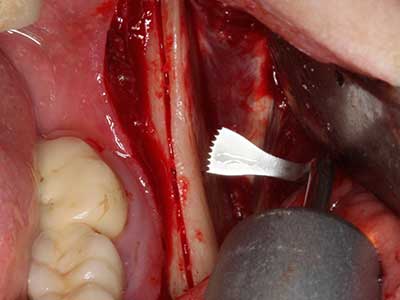

Fig. 18: Preparación de una tapa cortical con la sierra ósea piezoeléctrica (Piezomed, W&H).